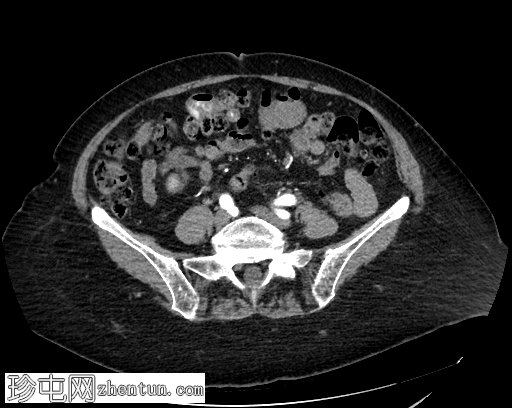

轴位增强扫描

门静脉期

横结肠中段可见一憩室,动脉期开始出现异常造影剂外渗,门静脉期增多,憩室腔内亦可见造影剂外渗,提示憩室出血伴活动性动脉出血。

患者既往有结肠憩室炎病史,此次因新鲜下消化道出血就诊。行CT血管造影以确定出血部位和出血来源。出血始于乙状结肠憩室,腔内渗出的造影剂与乙状结肠腔内的造影剂相连。随着造影剂显影的进行,憩室逐渐被完全充盈,乙状结肠腔内渗出的造影剂增多,符合活动性动脉出血的表现。